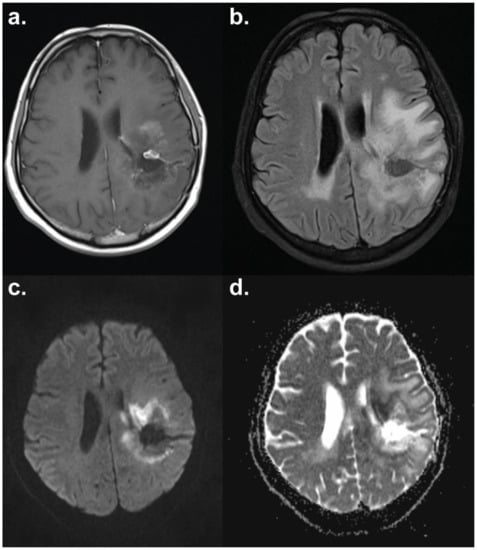

- Chu, H.H.; Choi, S.H.; Ryoo, I.; Kim, S.C.; Yeom, J.A.; Shin, H.; Jung, S.C.; Lee, A.L.; Yoon, T.J.; Kim, T.M.; et al. Differentiation of true progression from pseudoprogression in glioblastoma treated with radiation therapy and concomitant temozolomide: Comparison study of standard and high-b-value diffusion-weighted imaging. Radiology 2013, 269, 831–840. [Google Scholar] [CrossRef]

- Kim, J.Y.; Park, J.E.; Jo, Y.; Shim, W.H.; Nam, S.J.; Kim, J.H.; Yoo, R.E.; Choi, S.H.; Kim, H.S. Incorporating diffusion- and perfusion-weighted MRI into a radiomics model improves diagnostic performance for pseudoprogression in glioblastoma patients. Neuro-Oncology 2018. [Google Scholar] [CrossRef]

- Hein, P.A.; Eskey, C.J.; Dunn, J.F.; Hug, E.B. Diffusion-weighted imaging in the follow-up of treated high-grade gliomas: Tumor recurrence versus radiation injury. Am. J. Neuroradiol. 2004, 25, 201–209. [Google Scholar] [PubMed]

- Asao, C.; Korogi, Y.; Kitajima, M.; Hirai, T.; Baba, Y.; Makino, K.; Kochi, M.; Morishita, S.; Yamashita, Y. Diffusion-weighted imaging of radiation-induced brain injury for differentiation from tumor recurrence. Am. J. Neuroradiol. 2005, 26, 1455–1460. [Google Scholar] [PubMed]